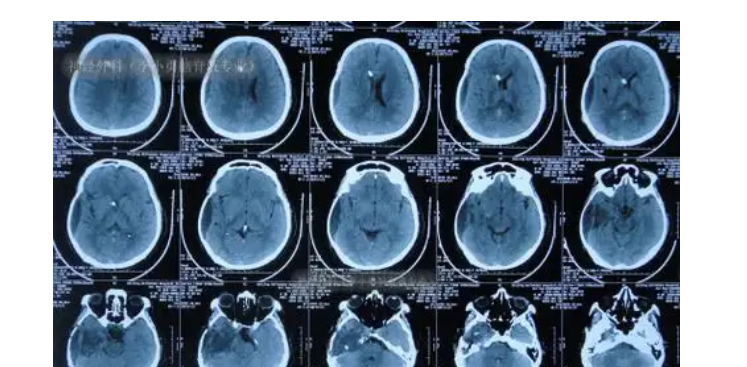

术后定期复查和评估非常重要,以便及时发现任何异常状况。复查项目可能包括核磁共振成像、血液检查等。及时发现复发或者转移的迹象,可以采取相应的治疗措施。